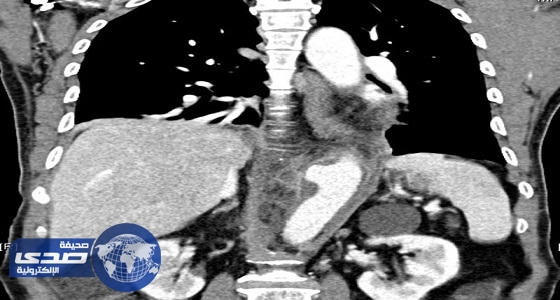

مستشفى بـ ” بيشة ” تستأصل ورم عمره 20 عام لخمسيني

منذ 7 سنة

1

3445